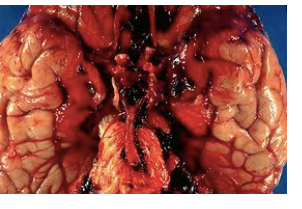

Name the stroke.

Subarachnoid hemorrhagic.